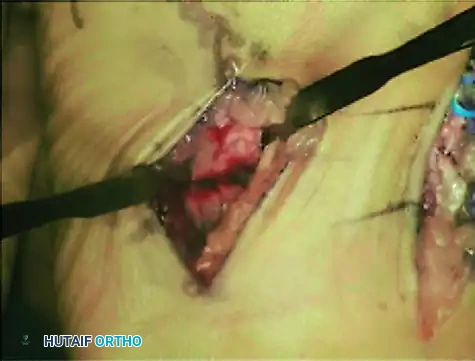

Intraoperative photograph demonstrating curettage and preparation of the second metatarsal. Note the blue vessel loop carefully retracting the dorsalis pedis artery and deep peroneal nerve away from the surgical field.